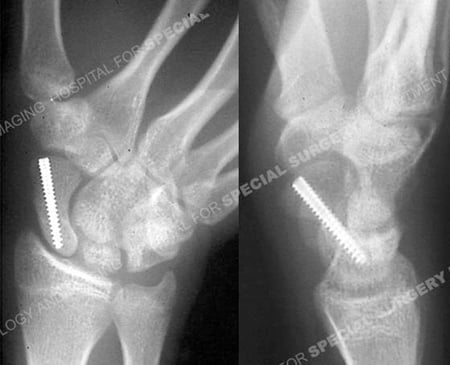

A 34-year-old male fell while snowboarding onto his outstretched right upper extremity and radiographs revealed a right-sided scaphoid fracture. He was referred to the care of Andrew J. Weiland, MD at the Orthopedic Trauma Service of Hospital for Special Surgery. Through a minimally invasive technique, the scaphoid fracture was anatomically reduced and fixed using a percutaneous headless screw. He continued to return at regular follow-up intervals and 4 months following fracture surgery, he presented with an excellent outcome including a healed scaphoid fracture, full range of motion, resolution of pain symptoms and return to all pre-injury activities.

Anteroposterior and lateral radiographs at 4 months illustrating a healed scaphoid fracture in anatomic alignment.